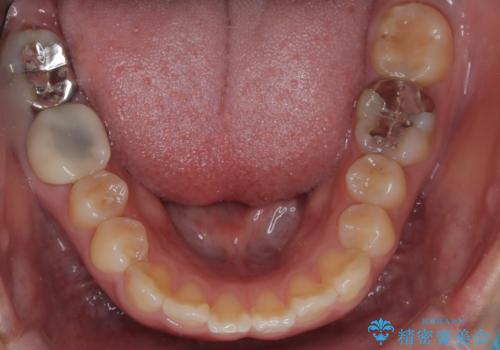

- 口元が出ている(突出している)ことを気にされて来院されました。精密な検査の結果、前歯を大きく後退させるスペースが必要と診断。患者様の**「前歯を下げたい」という強いご要望に応えるため、上下左右の第一小臼歯を抜歯し、そのスペースを利用して前歯を奥へ移動させる治療計画を立案しました。また、人目を気にせず治療できるよう、上顎に裏側矯正、下顎に表側矯正を組み合わせたハーフリンガル矯正**を提案しました。

今回の矯正治療では、前歯を大きく後退させるスペースを確保するため、計画通り上下左右の第一小臼歯を抜歯しました。装置には、上顎には目立たない裏側矯正(舌側矯正)を、下顎には透明な審美ブラケットを使用するハーフリンガル矯正を採用しました。抜歯によってできたスペースを最大限に活用し、前歯を効率よく後方へ移動。治療の結果、口元の突出感が大幅に解消され、Eライン(横顔の美しさの基準)も改善しました。人目を気にすることなく治療を完遂し、自信の持てる美しい横顔を獲得していただけました。